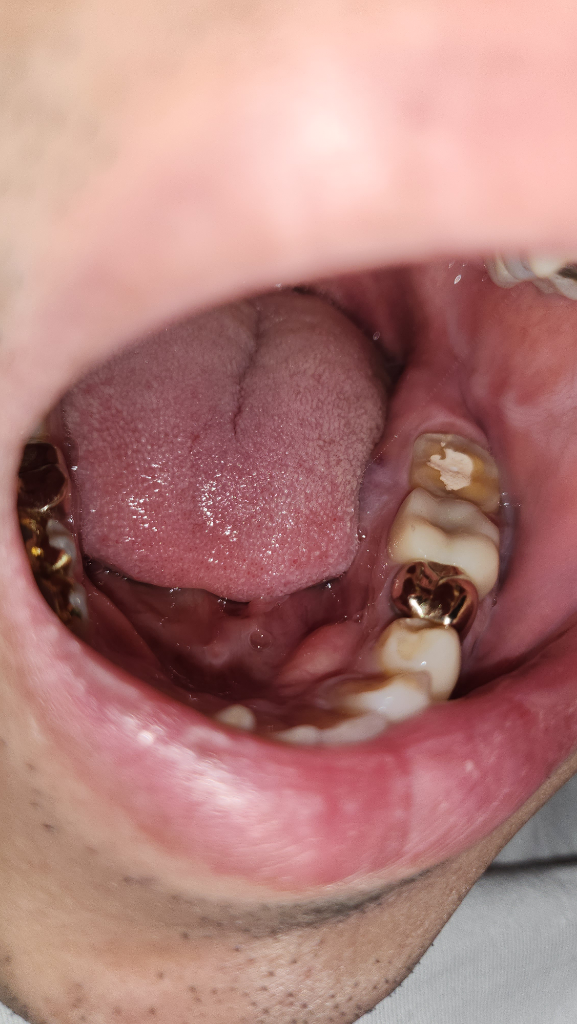

바깥쪽 볼은 손바닥을 대었을때 부은 느낌이 들고 치아 옆쪽 부분은 사진처럼 부음 증상이 생겼습니다

• 1번 째 사진